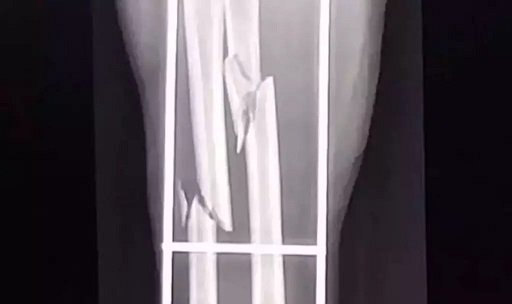

Radiografia mostra a fratura no braço da mulher (Foto: divulgação / Polícia Civil)

Conforme a Polícia Civil, a vítima e o marido estavam em casa, quando foram surpreendidos pelo suspeito e agredidos a pauladas. A mulher sofreu fratura no antebraço e o seu companheiro teve três costelas quebradas.

Ele foi detido e levado à delegacia, onde foi reconhecido por uma das vítimas. A mulher foi medicada e transferida para a unidade de saúde Três Lagoas, onde passará por cirurgia. O autor foi preso em flagrante por lesão corporal de natureza grave e permanece preso à disposição da justiça. Ele já tem passagens pela Polícia de São Paulo pela prática de furtos e roubos.